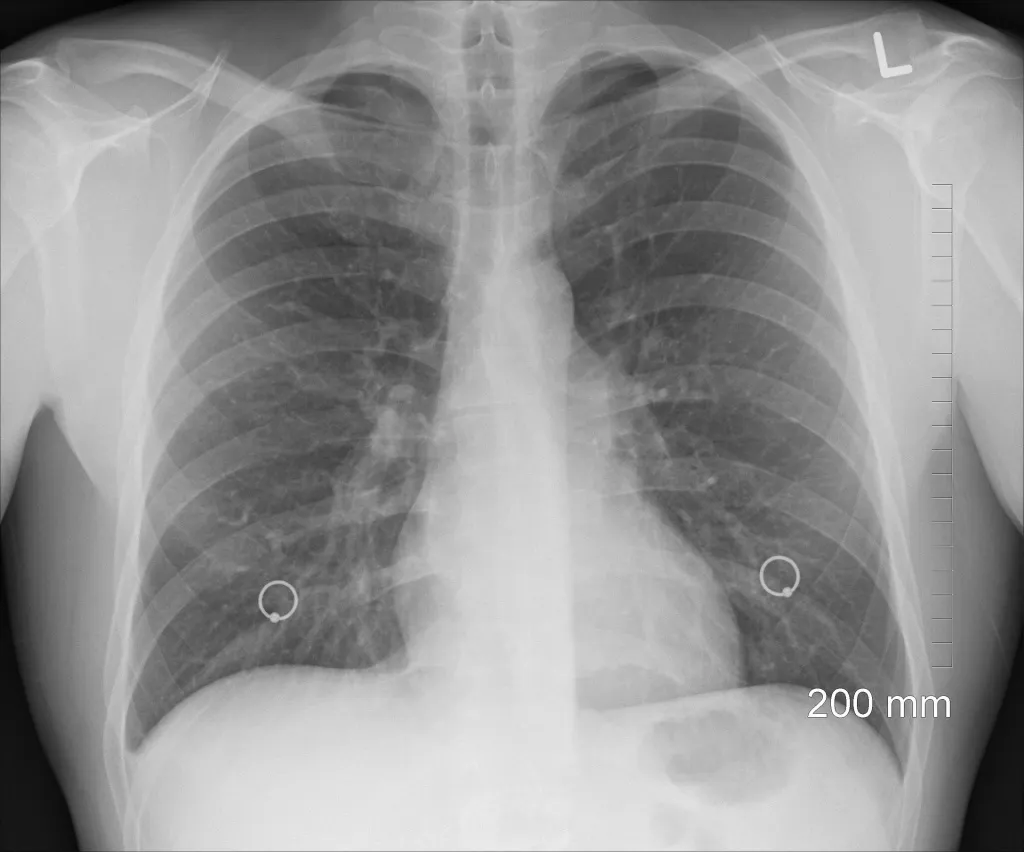

5. Флюорография органов грудной клетки выявляет туберкулез даже на ранних стадиях

- Флюорография позволяет выявить достаточно ранние формы туберкулеза, его начальные проявления - небольшие очаги в легких. Это достаточно надежный метод профилактического осмотра. Что касается детей, до 7 лет им проводят кожную пробу Манту, а после 8 лет - кожную пробу с диаскинтестом. Кожные пробы позволяют выявить у детей и подростков состояние инфицирования микобактериями туберкулеза, когда самого заболевания еще нет. Проведение профилактических мероприятий позволяет в большинстве таких случаев предотвратить развитие туберкулеза.